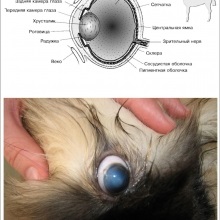

Cornea - a sűrű átlátszó lencse előtt helyezkedik el a szemgolyó. Ez egy nagyon fontos a szem szöveteire, annak átláthatóságát függ látást. A szaruhártya-gyulladás (keratitis) lehet az oka, hogy az expozíció a ugyanazon okokból, mint a kötőhártya-gyulladás, a gyulladást, valamint a szomszédos átmenet.

Volvulus század - helytelen pozícióban a század, amelyben van csomagolópapír szabad széle a szemgolyó. Ebben az esetben a szempillák és a haj sérülését a kötőhártya és a szaruhártya, ami a gyulladás. Egyes kutyafajták (shar pei, Chow Chow) egy veleszületett, azaz nyilvánul meg rövidesen.